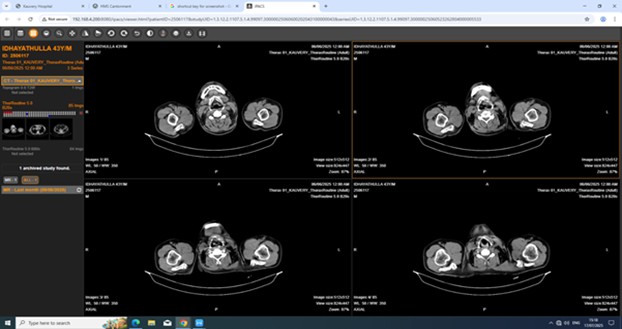

Imaging examination

CT Thorax

Reticular opacity with interstitial septal thickening with traction bronchiectasis in bilateral lung fields with subpleural and lower lobe predominance, Reactive mediastinal lymphadenopathy